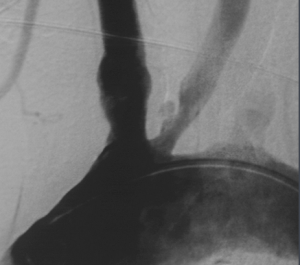

腦血管造影或都卜勒證實有顱內動脈狹窄者,藥物治療無效時,可考慮手術治療。